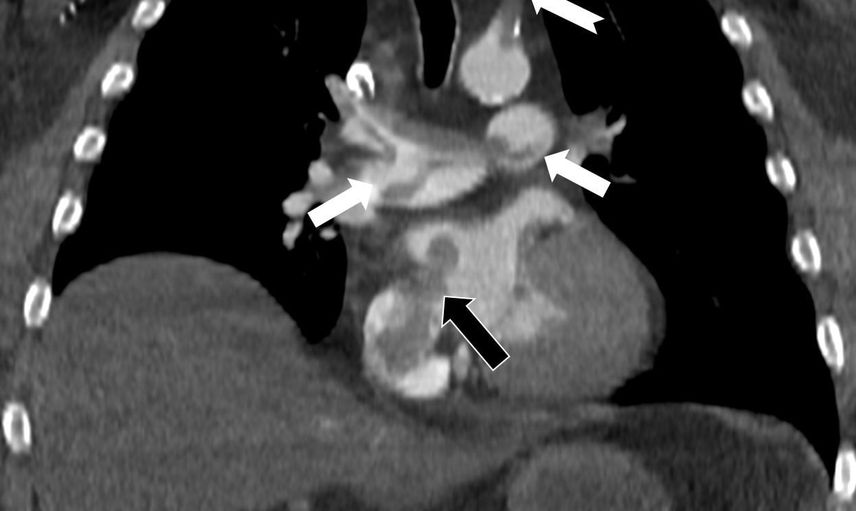

Çalışmada sunulan olguda, 60 yaşındaki bir hasta, penis ameliyatından 5 gün sonra ani göğüs ağrısı, nefes darlığı ve kol uyuşması şikâyetleriyle hastaneye başvurdu. Yapılan bilgisayarlı tomografi anjiyografisi incelemesi, toplar damarlardan kaynaklanan pıhtının akciğer damarlarını tıkadığını gösterdi. Aynı zamanda görüntüleme, pıhtının kalpte daha önce fark edilmemiş bir delikten (atriyal septal defekt) geçerek sağdan sola yönelip ana atardamara ulaşması ve sol kol damarını tıkaması bulgusunu ortaya koydu.

Prof. Dr. Karabulut’un çalışması, bacak damarlarından kaynaklanan pıhtıların yalnızca akciğer embolisine yol açmakla kalmayıp; kalp deliği varlığında ana atardamar yolu aracılığıyla beyin, kol ve bacak gibi bölgelere geçerek ani damar tıkanmasına (paradoks emboli) neden olabileceğini vurguluyor. Çalışmada, nedeni bilinmeyen pıhtı atmalarında kalpteki gizli deliklerin mutlaka araştırılması gerektiği belirtildi.

Makale, ekokardiyografi ve bilgisayarlı tomografi tetkiklerinin erken ve doğru tanı koymada hayat kurtarıcı rol oynadığını işaret ediyor; çalışmada bu görüntüleme yöntemlerinin birlikte kullanılmasının kritik olduğu vurgulanıyor.